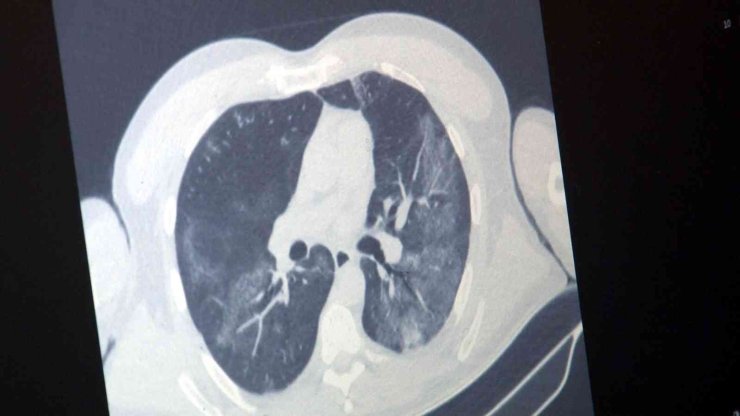

Kayseri Şehir Hastanesi Enfeksiyon Hastalıkları ve Klinik Mikrobiyoloji Bölümü'nden Uzman Dr. Esma Eryılmaz Eren, bulaşıcı bir solunum yolu hastalığı olan influenza hakkında bilgiler verdi. İnfluenzanın görüldüğü vaka sayısında bir artış yaşandığını kaydeden Eren, "Kış aylarının gelmesiyle birlikte insanların daha çok kapalı ortamlarda birlikte vakit geçirmesiyle beraber solunum yoluyla bulaşan virüslerin hepsinde artma görüyoruz. Bir yandan korona virüs salgını devam ederken bir yandan da epeydir vaka görmediğimiz influenza hastalarımız artan sıklıkla görülmektedir. Maskenin önemi halen devam ediyor. Biraz rahatlamayla maske kullanımı ve insanların kalabalık ortamda vakit geçirme süresi arttığı için solunum yoluyla bulaşan hastalıklar artıyor. Bunlardan en önemlisi influenzadır. Hasta insanların hapşırması ve öksürmesiyle havada asılı kalan damlacıklarla bu virüs bulaşıyor. Maske kullanımına da dikkat edilmediği zaman aldığımız nefesle beraber enfekte oluyoruz. Ateş ve öksürük ile devam ediyor. Ev içinde de bulaş mevcut. Ateş ve öksürük nedenli poliklinik başvurularımızda artış var. Bu şekilde vakalarımız artmış durumdadır" ifadelerini kullandı.

"Bu virüsün yıllardır uyguladığımız kendi aşısı var ama influenza vakalarını çok görmediğimiz için bu sene aşı sayısı oldukça azaldı. Bununda etkisiyle influenza vakalarımız epey artmış durumda. Domuz gribi influenzanın bir tipidir. Kuş gribi de influenzanın bir tipidir. Bu virüslerin genel ismi influenza virüsüdür. Korona virüste, influenza da solunum yoluyla bulaşır. Klinik durumda ayırt etmek oldukça zordur. Her ikisi de akciğer tutulumu ve ateş yapabilir. İnfluenza da eklem ağrılarını biraz daha fazla görüyoruz. Tat ve koku kaybı influenza da çok beklediğimiz bir durum değil. İnfluenza özellikle gebelerde, 65 yaş üstünde, KOAH'ı ve diyabeti olan hastalarda daha ağır seyreder. Buna dikkat etmek gerekir. Vatandaşlarımız maske kullanmaya dikkat etsinler. Kapalı ve kalabalık ortamlardan mümkünse uzak dursunlar. El hijyeninin önemi de halen devam ediyor."